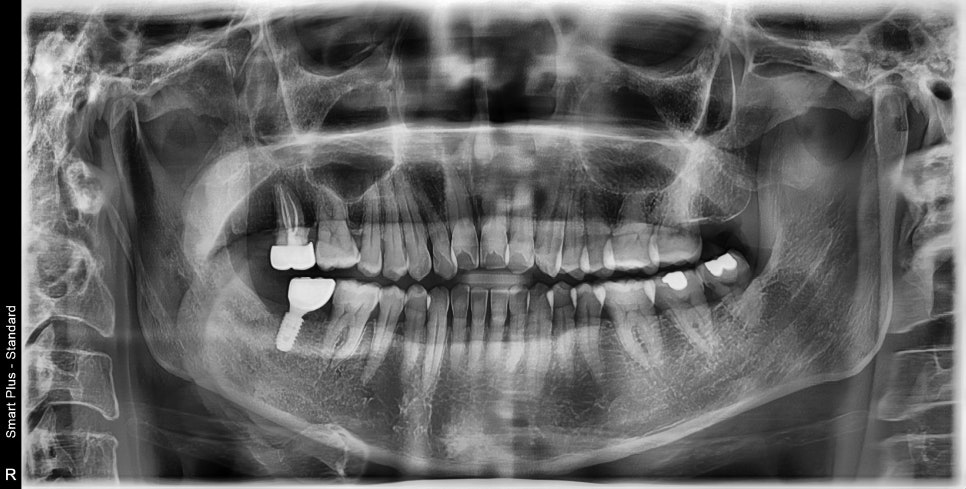

크라운치료 후 확보된 공간의 임플란트 치료

부족한 공간을 위해 대합 치아의 크라운치료가 필요했습니다.

정출양이 많았기 때문에 신경치료는 불가피했습니다.

다행히 충분하게 확보된 공간에 임플란트 보철도 안정적으로 완성할 수 있었습니다.

치아의 높이를 이상적으로 맞춰 교합 형성도 용이하게 할 수 있었습니다.